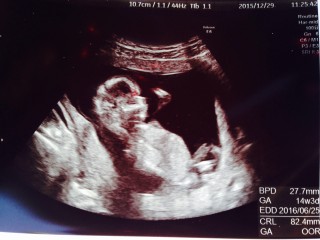

体外受精で授かりました。 82.4㎜で順調だそうです(^^) 4Dエコーでは、顔立ちがはっきり見えてきました♪ マタニティヨガやビクスの教室にも参加OKと言われました♪